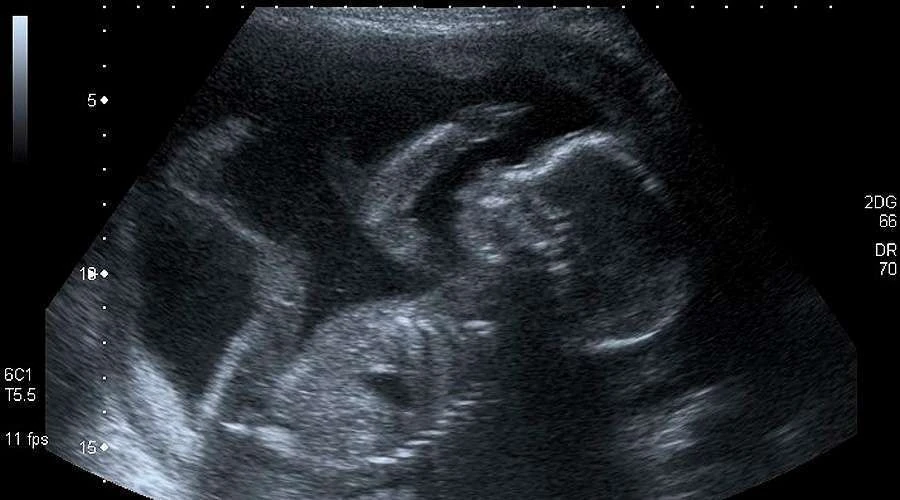

7.- Manipula los resultados de las ecografías“Se deberá explicar a la usuaria su derecho a solicitar no ver las imágenes ni escuchar los sonidos. En caso de realizarse la ecografía, solo se compartirán con la persona la imagen o el sonido de los latidos si ella lo solicita expresamente. Si no lo hace, es de suma importancia tomar los recaudos necesarios para que aquello no suceda”, describe el protocolo en la página 38.

“A su vez, si es posible, facilitar distintas áreas donde se puedan evaluar separadas aquellas mujeres que buscan una interrupción de aquellas que reciben cuidados prenatales”, agrega.